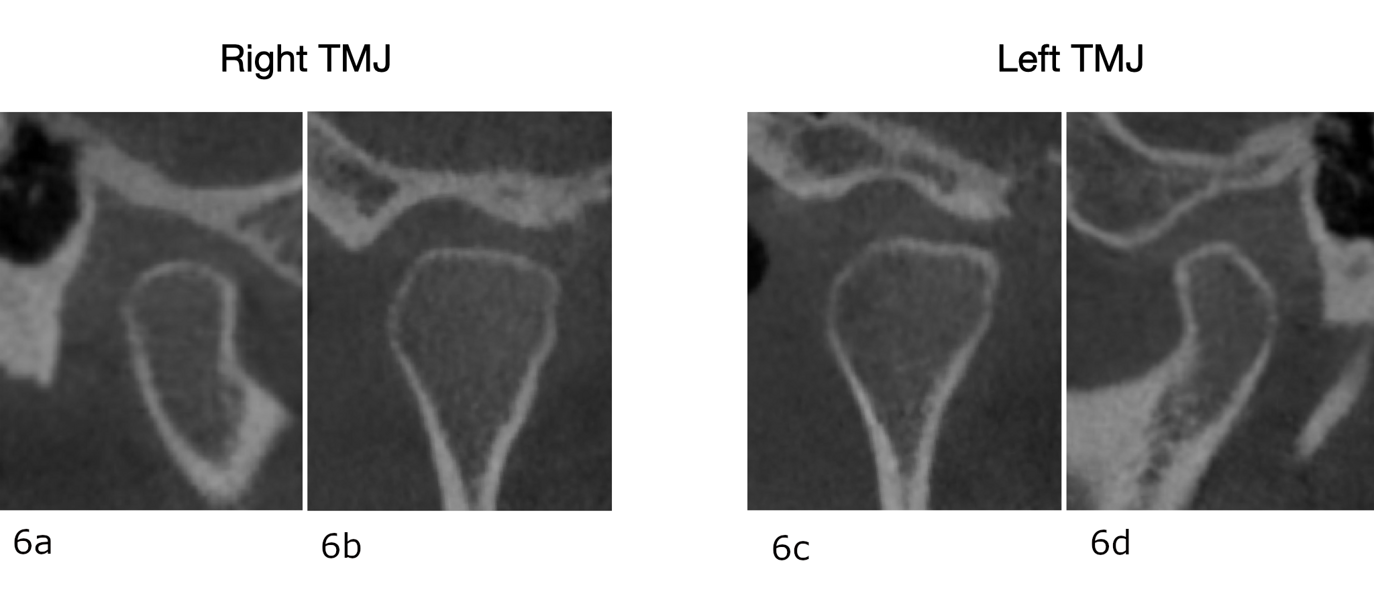

The CBCT scan of the condyles after splint therapy showed a more normal position of the condyles54 with respect to the fossae, as well as greater corticalisation of the right condyle (Fig. 41). In addition, the condylar graphs of the 4D images showed a significant improvement of the condylar movement, having a more uniform and anatomical trajectory during opening and closing and achieving condylar rotation (Figs. 42 & 43).

After treatment, the patient had bilateral Class I molar and canine relationships, correct overjet and overbite, centred midlines and improved arch forms (Fig. 52). Extra-orally, she had improved arch forms, a wider smile, an improved smile line and less gingival exposure (Fig. 53). The lower facial third had been shortened thanks to mandibular antero-rotation, and there was improvement of the upper lip support thanks to the positive torque of the maxillary incisors. In the post-treatment panoramic radiograph, we observed excellent periodontal status, no resorption of the roots and extraction of the maxillary third molars (Fig. 54). In the post-treatment cephalometric tracing, we saw a decrease of the ANB angle, a reduction in the anterior face height, an increase of the facial axis angle, and a decrease in the distance between the soft pogonion and the true vertical line thanks to the anticlockwise rotation of the mandible (Fig. 54). We also found an increase in the inclination of the maxillary incisors and an improvement in the final inter-incisal angle. Concerning her TMJs, the patient remained totally asymptomatic and had a vertical masticatory pattern and a stable arc of closure. The CBCT scan showed well-corticated condyles in the same position as that obtained after the splint therapy (Fig. 56).